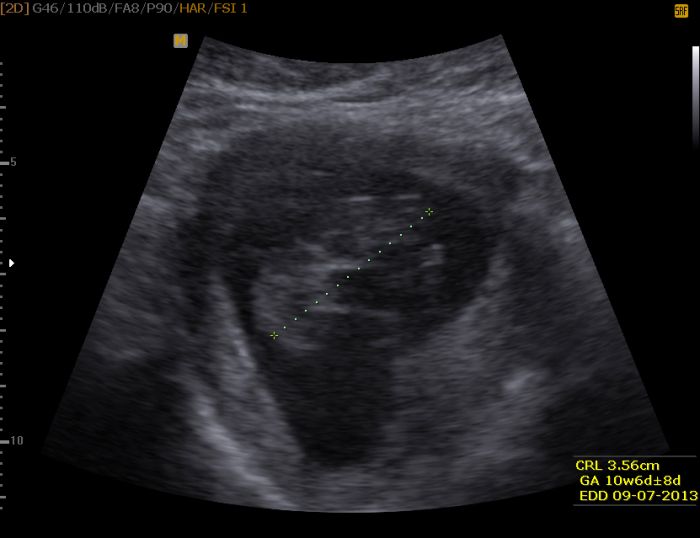

Byla jsem na kontrole 17.12, dostala průkazku a jsme v 10+6. Paní doktorka mi nahrála fotečky i video a konečně je mohl manžel vidět. Poslední vám sem vložím. Těším se na scrinning kam jdeme 28.12. ale nevím co tam přesně uvidím. Jelikož jsem prvorodička a nevím co a jak tak nemám vůbec strach jsem v klidu a děsně vysmátá. Nevolnosti mě minuly, chutě nemám jen potřebuji vysondovat nějakou dobrou mast na prsa. Jsou v jednom ohni citlivé, bolestivé a vysušené kolem bradavek.